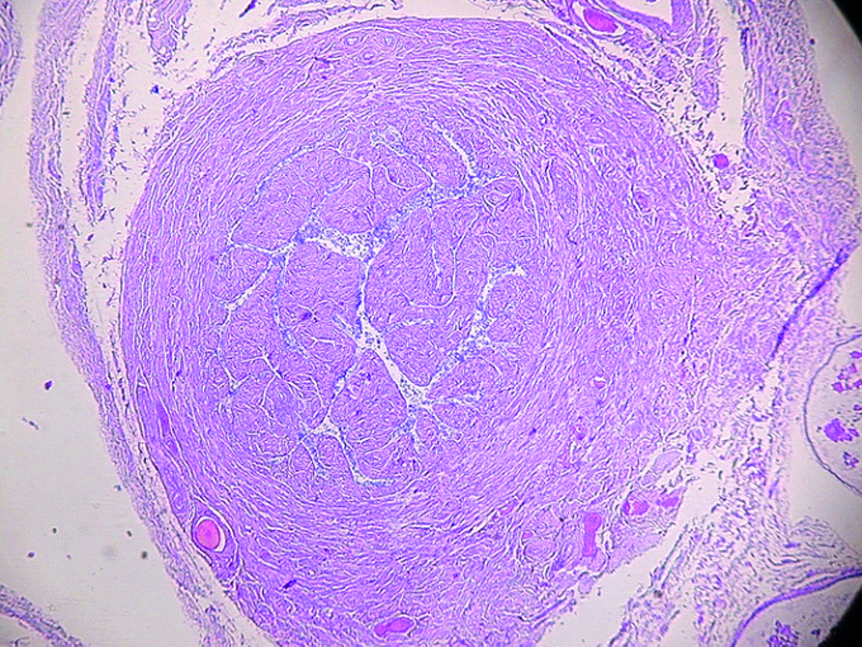

Выявлено, что эпителий маточных труб у женщин II и особенно III исследуемых групп выглядит более уплощенным. При этом складки слизистой оболочки более толстые, чем на препаратах маточных труб женщин I группы. Именно такая гистологическая картина ярко выражена в перешейке маточных труб женщин старческой возрастной группы. Кроме того, сами складки имеют близкое расположение по отношению друг к другу и частично сливаются между собой. Это является причиной неравномерного сужения просвета перешейка маточной трубы (рисунок 2).

Рисунок 2. Фрагмент перешейка маточной трубы женщины в возрасте 86 лет. Окраска гематоксилином и эозином. ×10.

Figure 2. A fragment of the isthmus of the fallopian tube of a woman aged 86 years. Staining with hematoxylin and eosin.10x.